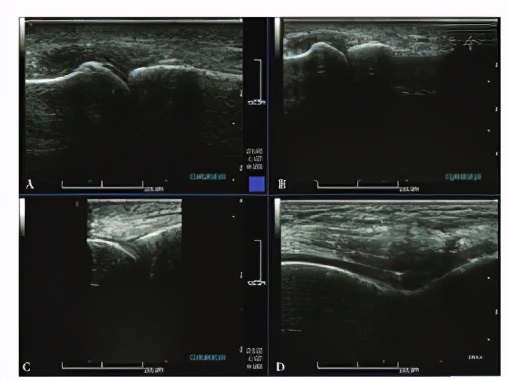

中国人民解放军南部战区总医院门诊及入院的相关检查:入院前3 d门诊空腹测尿酸628 μmol/L,入院后第7天测空腹尿酸525 μmol/L,门诊空腹血糖5.7 mmol/L。膝关节+踝关节CT示双侧髌股关节、左踝及左足骰骨-第4跖骨关节骨性关节炎表现;双膝、双踝及双足周围散在点状绿染结节,以右膝关节为甚,考虑少许痛风石形成(见图1)。双足超声示双侧第一跖趾关节表面有钙盐沉积(考虑痛风可能性大);双足疼痛处皮下距骨表面滑膜增生(见图2)。双下肢血管超声提示血流通畅。泌尿系超声示双肾有小结石。肾血流图提示肾功能轻度受损。血浆白蛋白、自身免疫的相关抗体、甲状腺功能指标、高敏肌钙蛋白和心电图均正常。入院后予以消炎、镇痛、碱化尿液、护胃抑酸等治疗,患者双下肢疼痛好转后加用降尿酸药物治疗;1周后患者病情稳定出院,嘱其纠正不良饮食习惯、多运动并继续降尿酸药物治疗;患者ED于泌尿外科门诊随诊,拟首选药物治疗,必要时结合患者意愿可行阴茎假体植入术。本例患者选择药物治疗ED,出院后随访3个月,ED未恢复。

图2 跖趾关节和膝关节表面超声图像

Figure 2 Ultrasonic images of the surface areas of metatarsophalangeal and knee joints of our case of gouty arthritis with erectile dysfunction